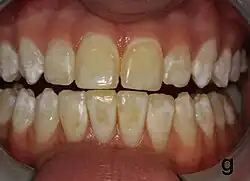

Dental fluorosis appears as a range of visual changes in enamel[4] causing degrees of intrinsic tooth discoloration, and, in some cases, physical damage to the teeth. The severity of the condition is dependent on the dose, duration, and age of the individual during the exposure.[1] The "very mild" (and most common) form of fluorosis, is characterized by small, opaque, "paper white" areas scattered irregularly over the tooth, covering less than 25% of the tooth surface. In the "mild" form of the disease, these mottled patches can involve up to half of the surface area of the teeth. When fluorosis is moderate, all of the surfaces of the teeth are mottled and teeth may be ground down and brown stains frequently "disfigure" the teeth. Severe fluorosis is characterized by brown discoloration and discrete or confluent pitting; brown stains are widespread and teeth often present a corroded-looking appearance.[1]

Diagnosis

The adequate diagnosis of fluorosis can be diagnosed by visual clinical examination. This requires inspection of dry and clean tooth surfaces under a good lighting.[6] There are individual variations in clinical fluorosis manifestation which are highly dependent on the duration, timing, and dosage of fluoride exposure. There are different classifications to diagnose the severity based on the appearances. The clinical manifestation of mild dental fluorosis is mostly characterised a snow flaking appearance that lack a clear border, opaque, white spots, narrow white lines following the perikymata or patches as the opacities may coalesce with an intact, hard and smooth enamel surface on most of the teeth.[7] With increasing severity, the subsurface enamel, all along the tooth becomes more porous. Enamel may appear yellow/brown with discolouration and/or many pitted white-brown lesions similar to cavities. They are often described as "mottled teeth".[8] Fluorosis does not cause discolouration to the enamel directly, as upon eruption into the mouth, affected permanent teeth are not discoloured yet. In dental enamel, fluorosis causes subsurface porosity or hypomineralizations, which extend toward the dentinal-enamel junction as the condition progresses and the affected teeth become more susceptible to staining. Due to diffusion of exogenous ions (e.g., iron and copper), stains develop into the increasingly and abnormally porous enamel.[7]